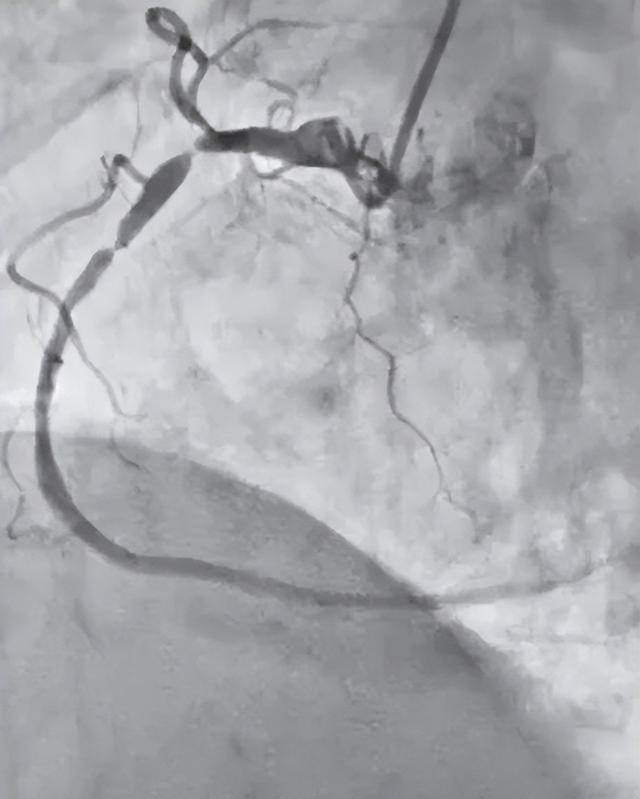

介入团队默契配合,凭借扎实的技术稳步推进手术,在局麻下精准穿刺血管,造影显示右冠状动脉近中段狭窄50-99%,远段狭窄40%,后降支近段狭窄85%。

(治疗前)

沿导丝送入预扩球囊至狭窄处预扩,再将支架精准覆盖狭窄处释放。再次造影示支架内未见残余狭窄,堵塞的冠状动脉被顺利开通,患者胸痛症状当场得到缓解。